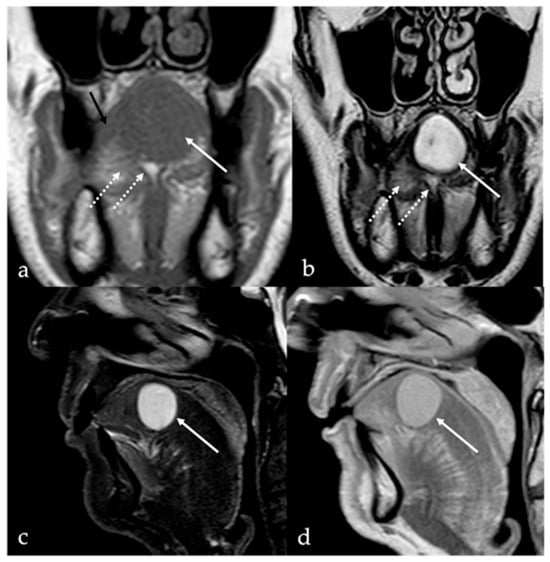

3. Schwannoma

5.1. Venous Malformations

| Schwannoma [6,7] | CT: hypodense MRI: high T2 SI, split fat, target and fascicular signs | Venous malformation, dermoid cysts, lipoma |

| Venous malformation [1,9] | CT: phleboliths MRI: high T2 SI, +CE | Other vascular malformations, schwannoma, dermoid cysts |